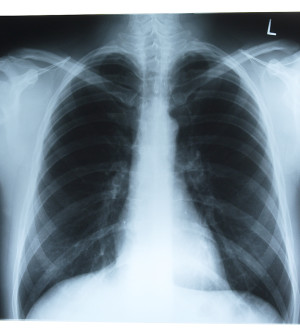

Cystic fibrosis is a genetic disease that causes serious lung and digestive problems. Using patient data from the patient registry of the Cystic Fibrosis Foundation, researchers examined all California residents diagnosed with the disease as children between 1991 and 2010. Overall, more than 1,700 patients were included in the study; 28 percent were Hispanic.